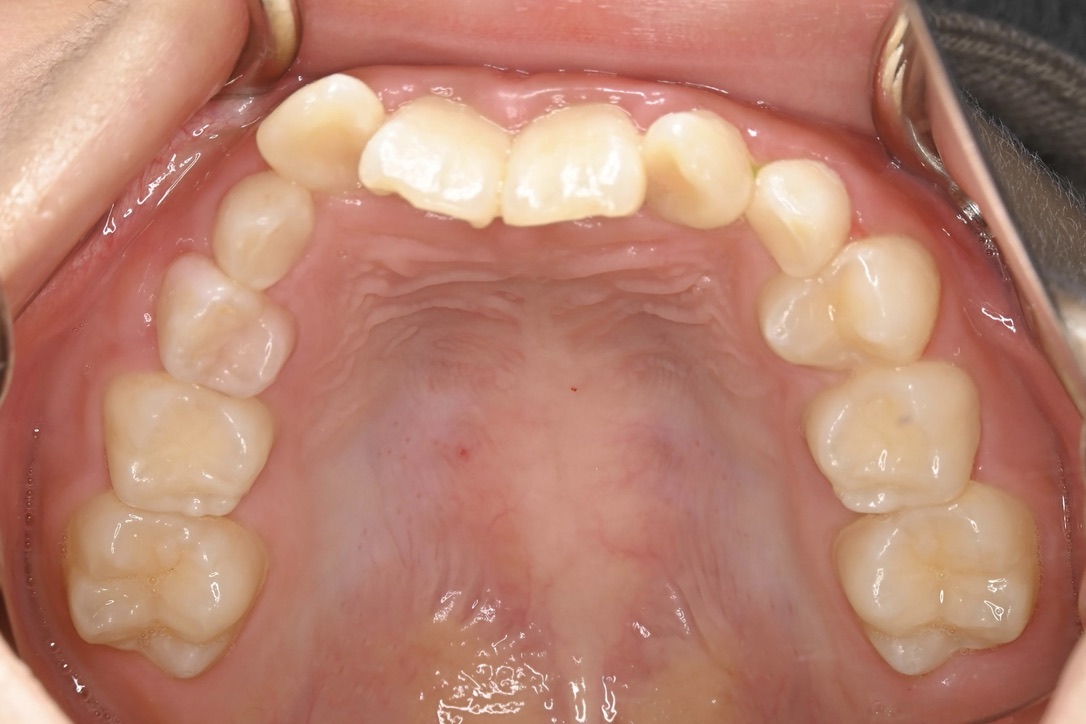

BEFORE

主訴 通っている歯医者で矯正した方がいいと言われて気になっている。下の前歯がでこぼこしている。

診断名・主な症状 下顎前歯の叢生を伴う過蓋咬合

治療内容 上下の歯並びの幅を拡げつつ、前歯の関係を改善しました。

使用装置 急速拡大装置

リンガルアーチ

機能的矯正装置(マイオブレース)